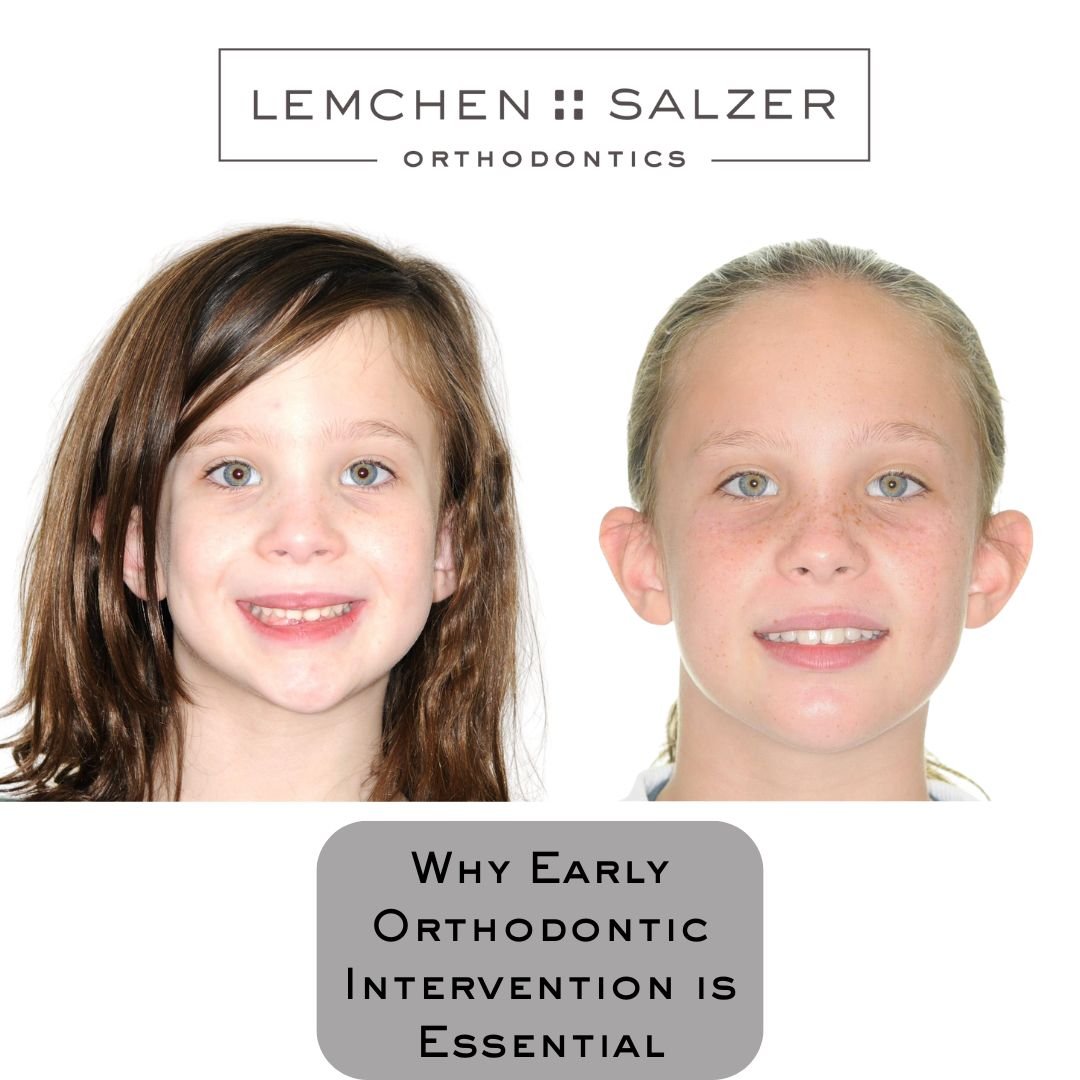

Why Early Orthodontic Intervention is Essential: A Case Study

Why Should My Six Year Old See An Orthodontist?

Early orthodontic assessment and, if necessary, treatment can make a significant difference in a child's dental development and overall facial balance. Dr. Salzer examined a case of a six-year-old patient whose initial evaluation revealed early signs of severe crowding and jaw alignment concerns.